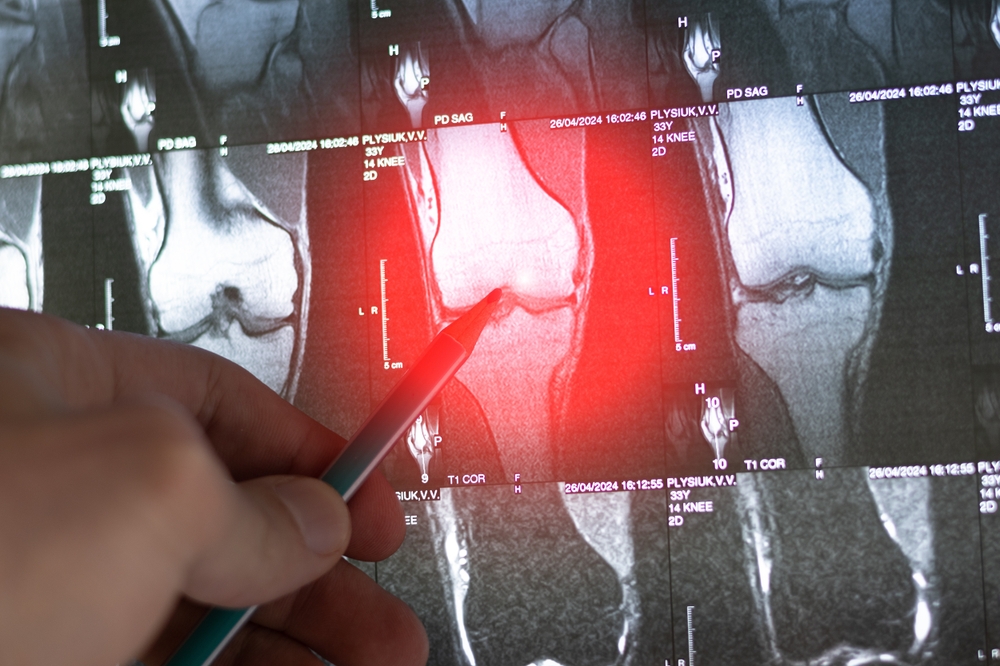

- Vaizdiniai tyrimai – rentgeno nuotraukos, kompiuterinė tomografija ar magnetinis rezonansas, leidžiantys pastebėti skaidulinio audinio sankaupas ar kaulų deformacijas